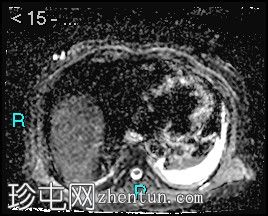

轴位

弥散加权成像 (DWI)

3.jpg

胰腺钩突附近可见边界不清的肿块,T2加权像呈不均匀中等信号,弥散受限明显。肿块大小为4.1 x 5 x 3 cm(前后径 x 横径 x 头尾径)。伴有胰管扩张,直径约6 mm。

肝脏可见多个大小不一的可疑病灶(从亚厘米级到2厘米不等)。T2加权像呈高信号,弥散受限明显。